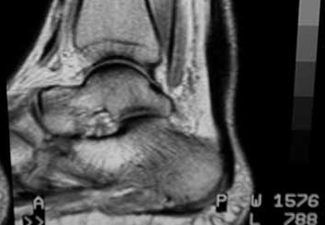

Resonancia magnética nuclear donde se observa el engrosamiento del tendón de aquiles.